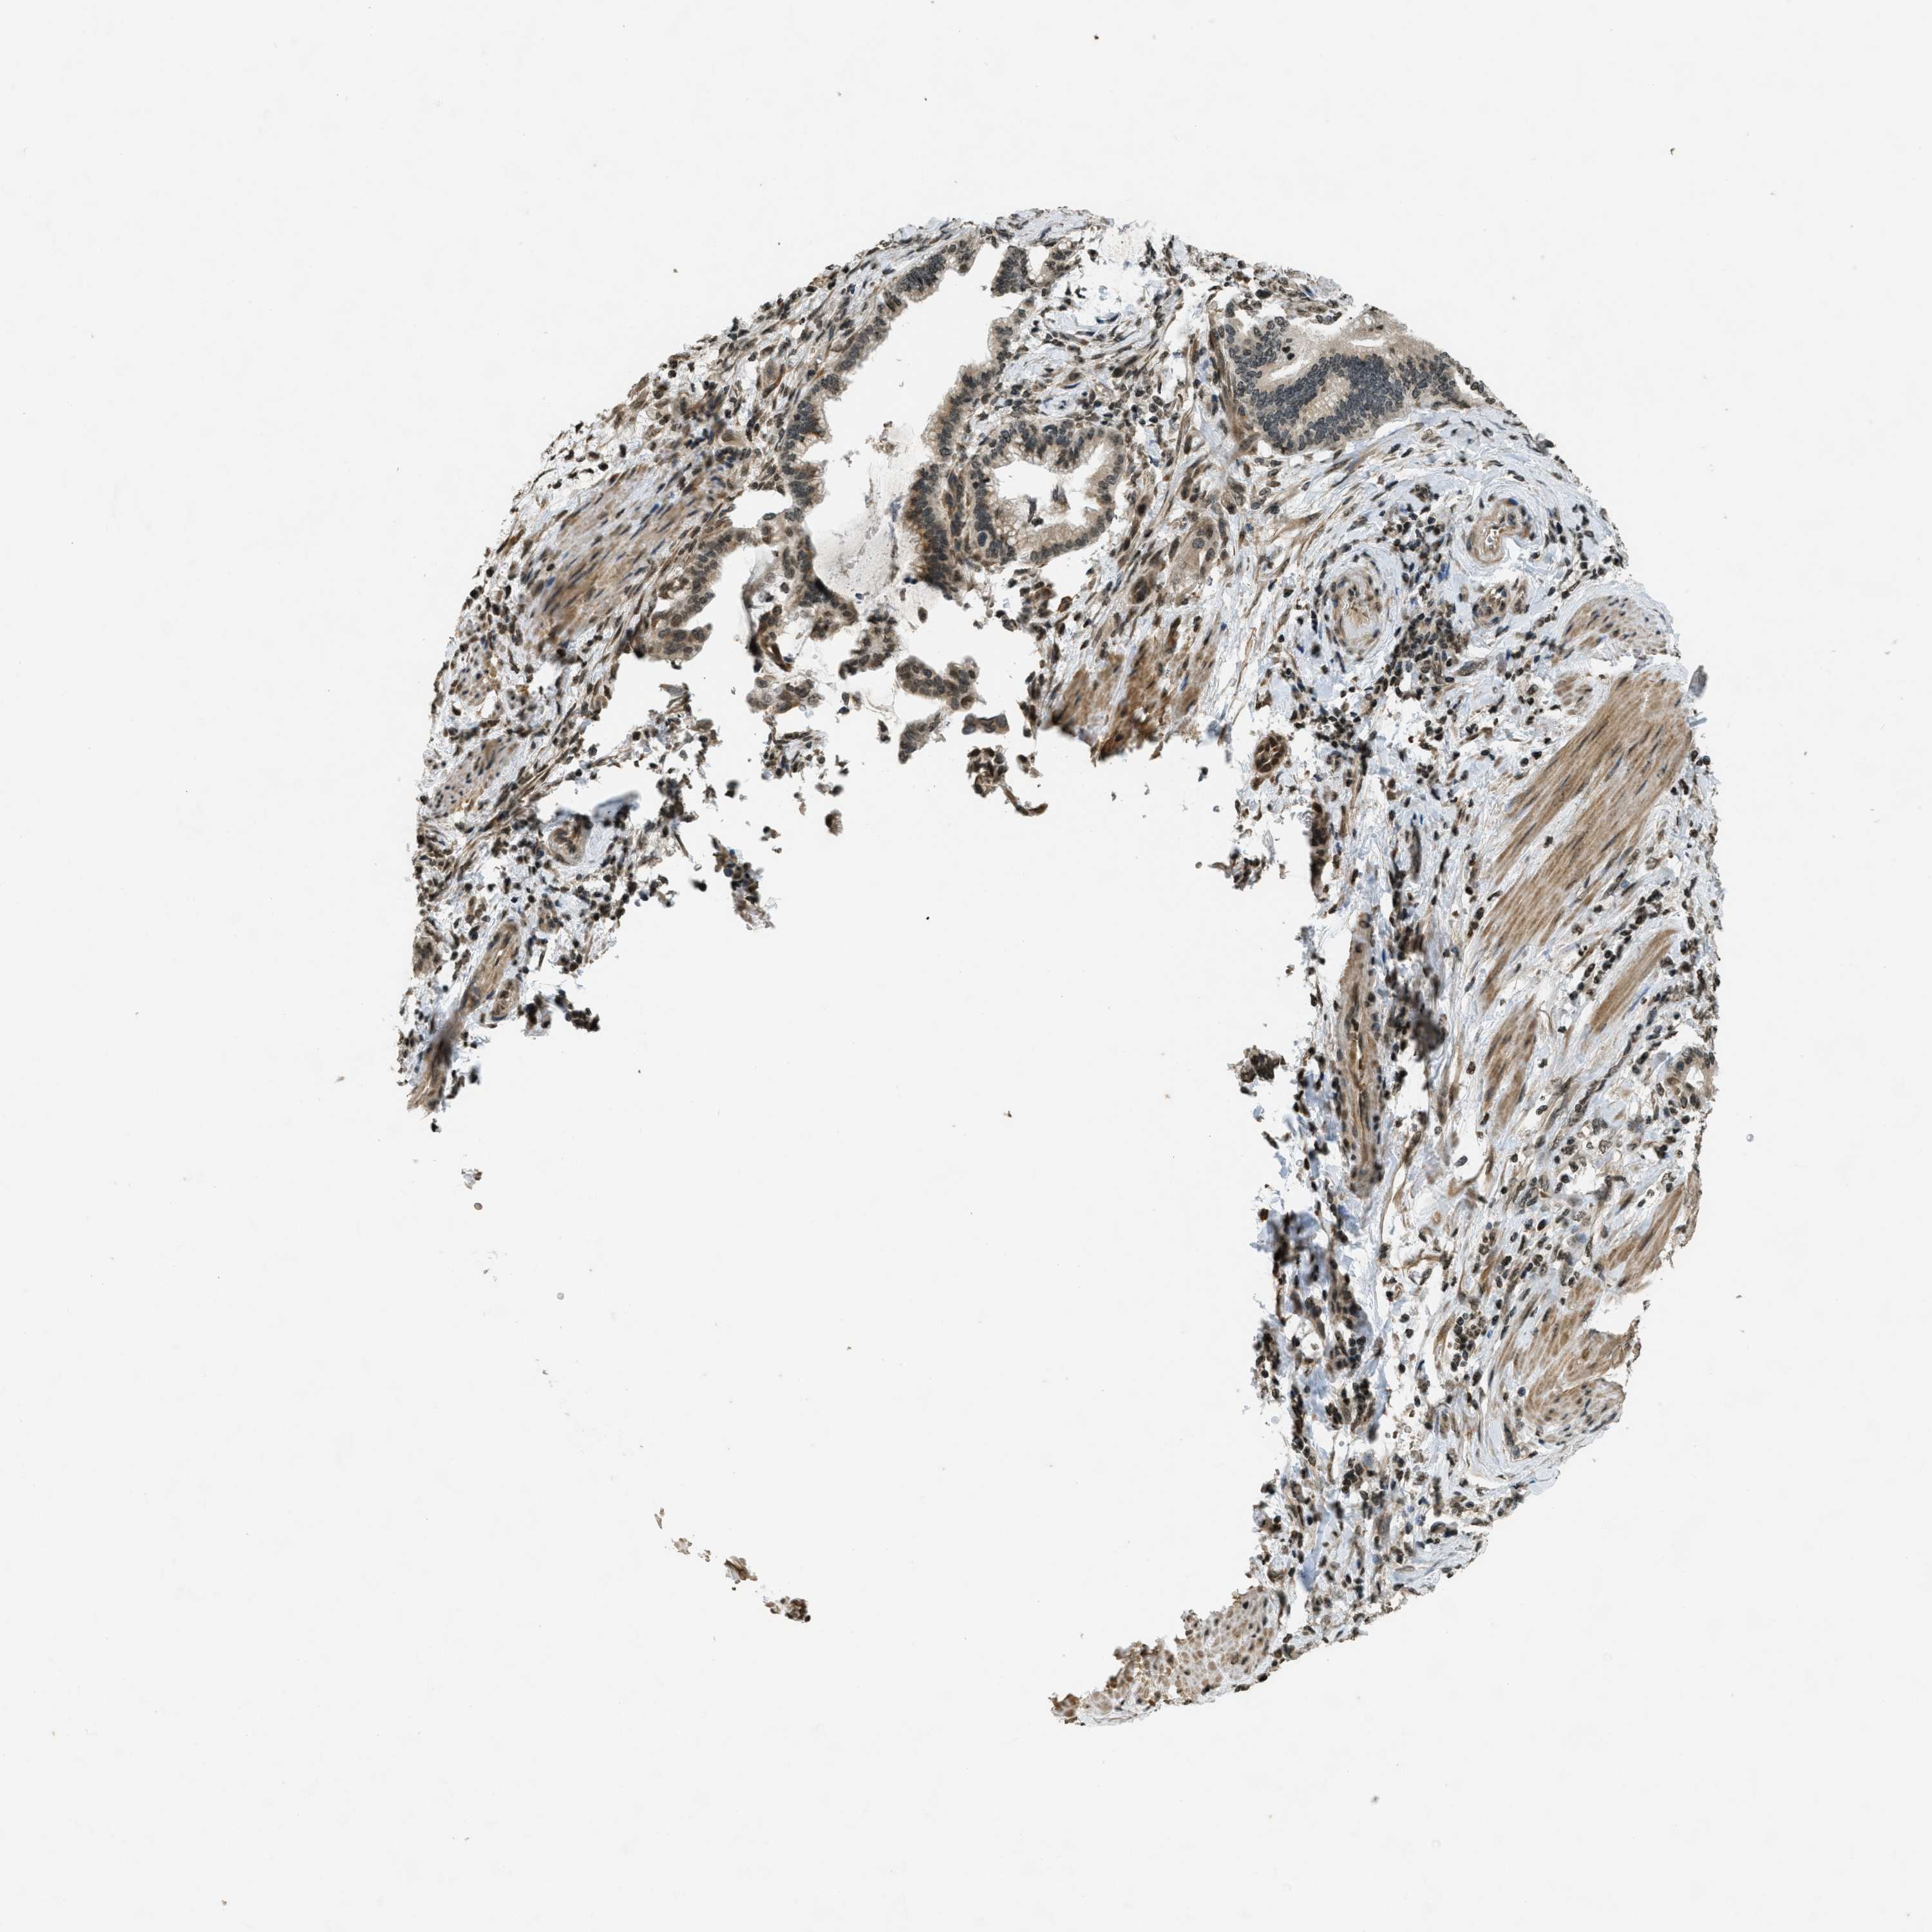

PANCREATIC CANCER - Protein expressioni

A mouse-over function shows sample information and annotation data. Click on an image to view it in a full screen mode. Samples can be filtered based on level of antibody staining by selecting one or several of the following categories: high, medium, low and not detected. The assay and annotation is described here.

Note that samples used for immunohistochemistry by the Human Protein Atlas do not correspond to samples in the TCGA dataset.

Antibody stainingi

Antibody staining in the annotated cell types in the current human tissue is reported as not detected, low, medium, or high, based on conventional immunohistochemistry profiling in selected tissues. This score is based on the combination of the staining intensity and fraction of stained cells.

Each image is clickable and will lead to virtual microscopy that enables deeper exploration of all samples and also displays staining intensity scores, fraction scores and subcellular localization as well as patient and tissue information for each sample.

Antibody HPA004246

Antibody CAB018641

Staining

High

Medium

Low

Not detected

Intensity

Strong

Moderate

Weak

Negative

Quantity

>75%

75%-25%

<25%

None

Location

Nuclear

Cytoplasmic/membranous

Cytoplasmic/membranous,nuclear

Adenocarcinoma, NOS

Adenocarcinoma, metastatic, NOS